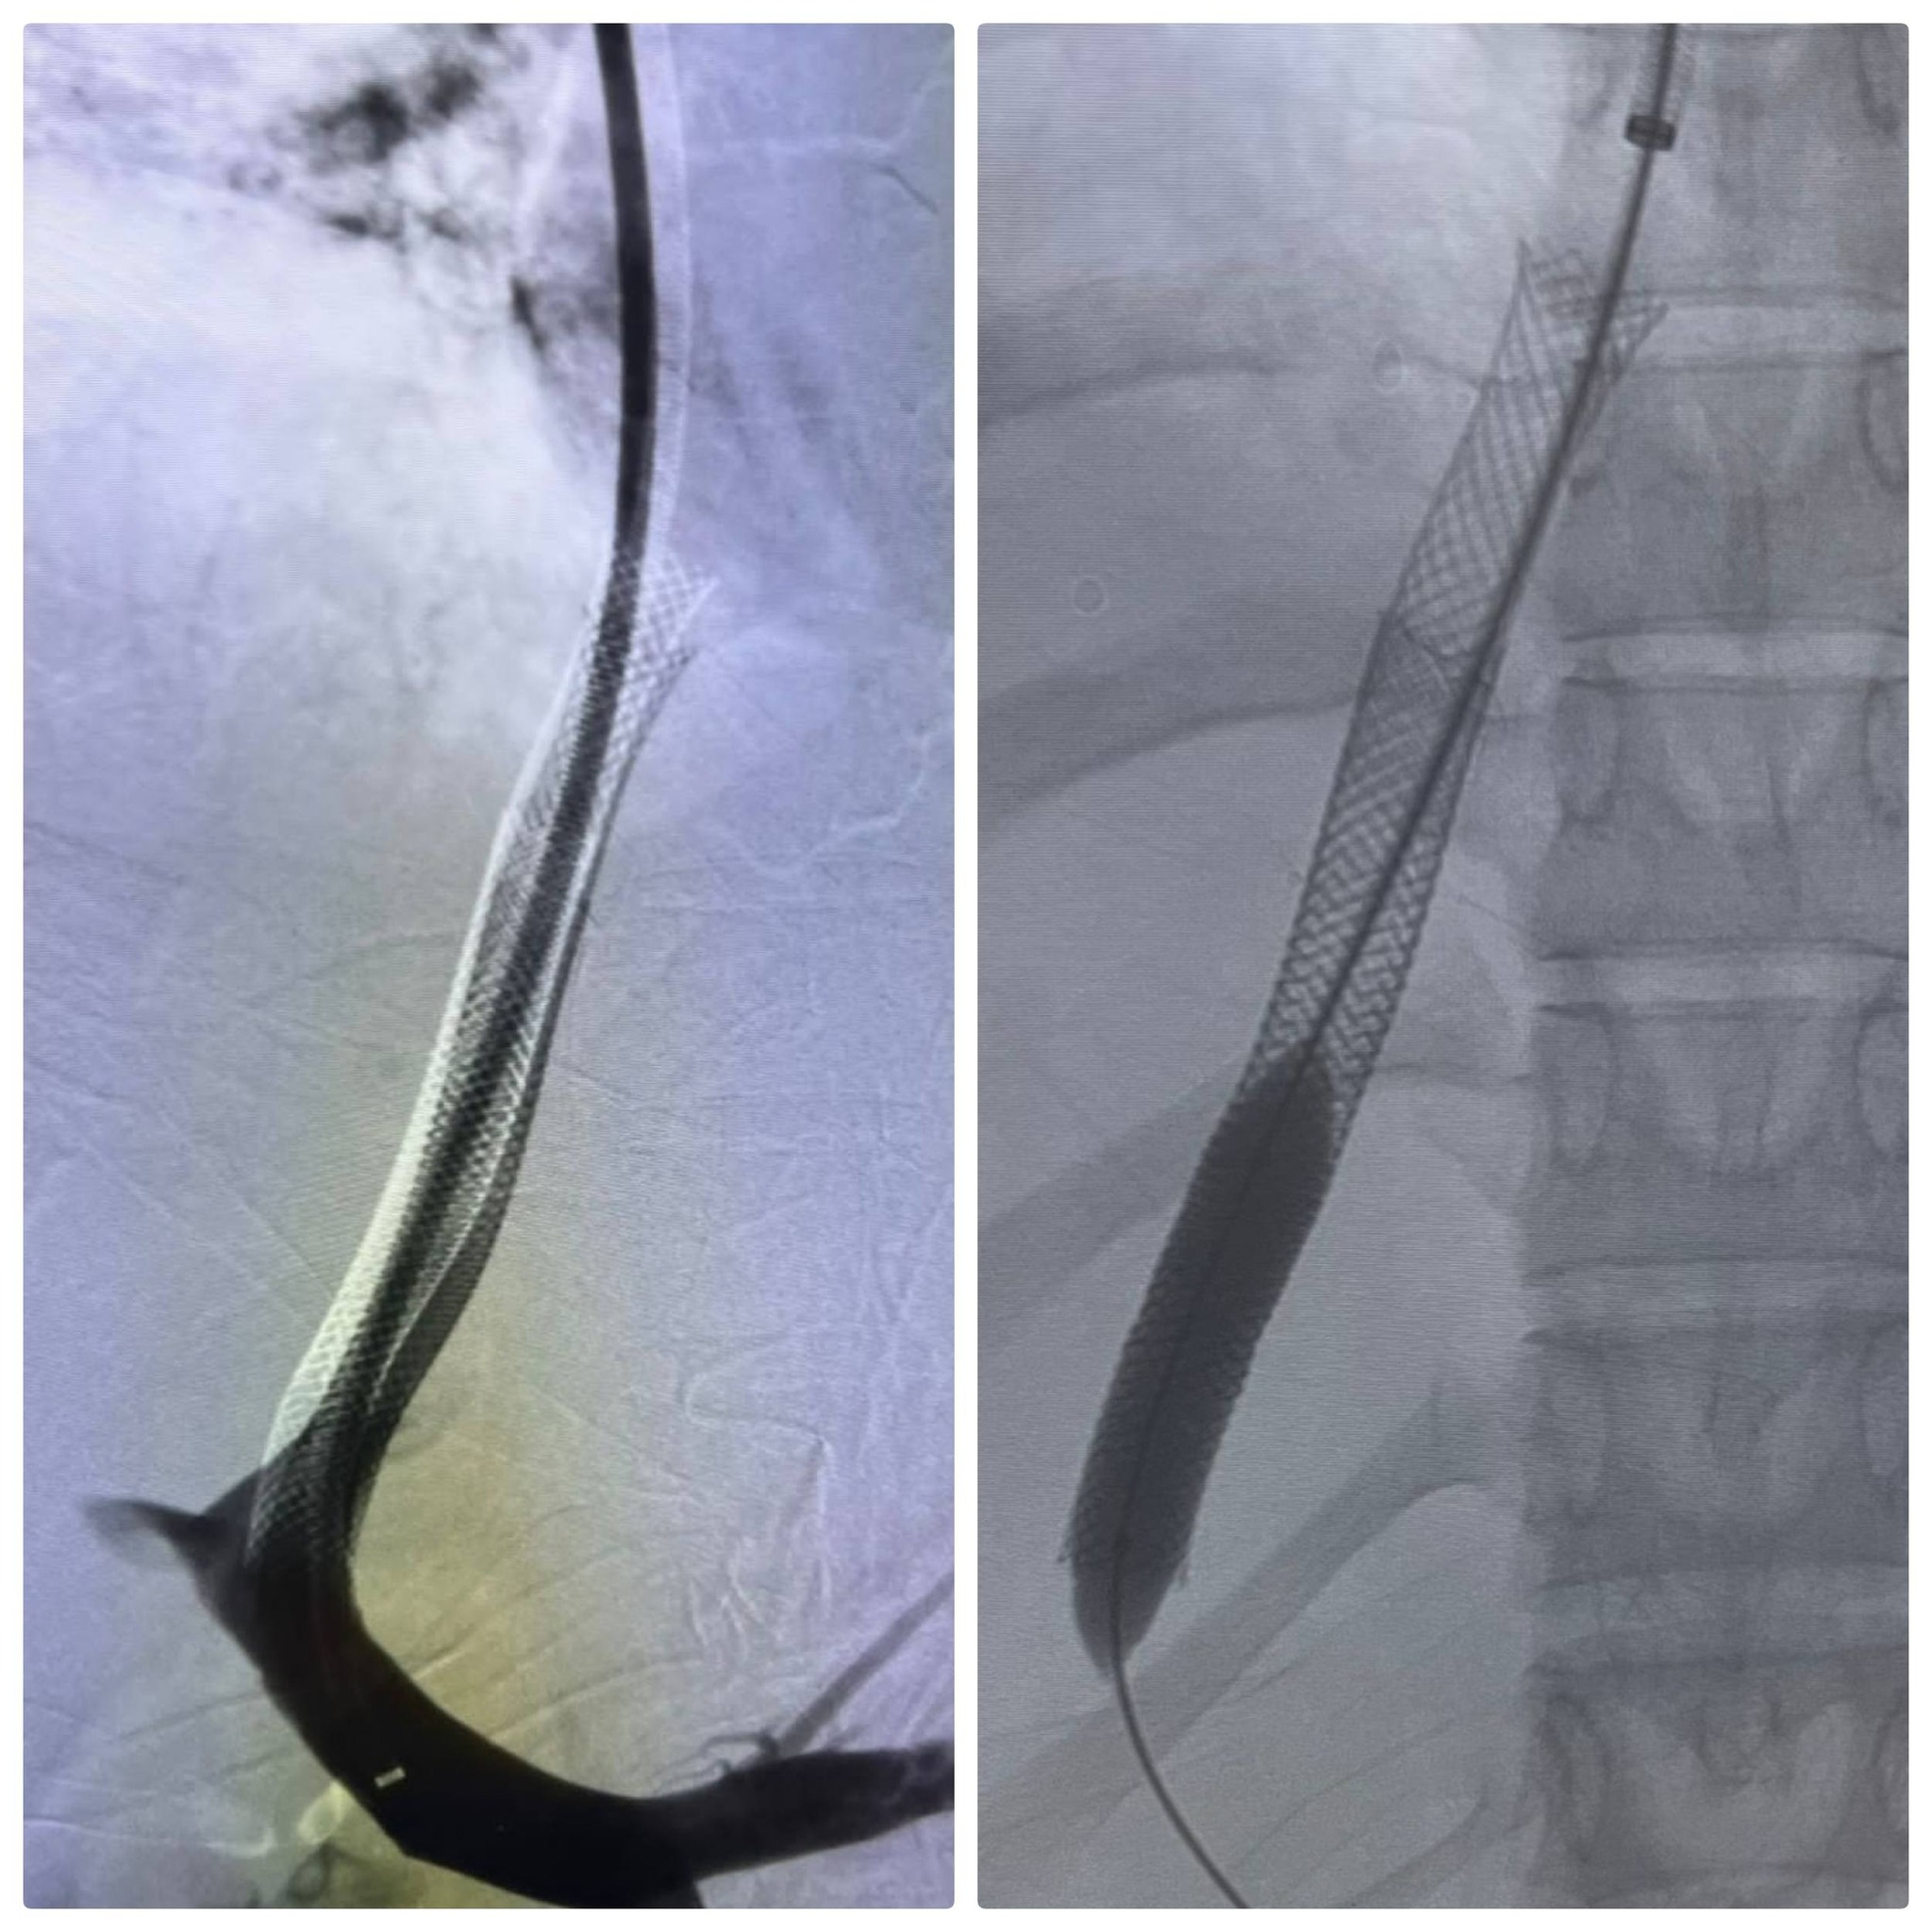

قام الفريق الطبي بإجراء عملية دقيقة لتركيب دعامات معدنية بين الوريد الأجوف السفلي والوريد البابي الكبدي باستخدام تقنية الـ (TIPSS)، والتي تُعد خياراً علاجياً متقدماً ينفرد به مستشفى الراجحي كونه المركز الوحيد في صعيد مصر الذي يقدم هذه التقنية التي تتطلب مهارة ودقة فائقة وتجهيزات طبية خاصة.